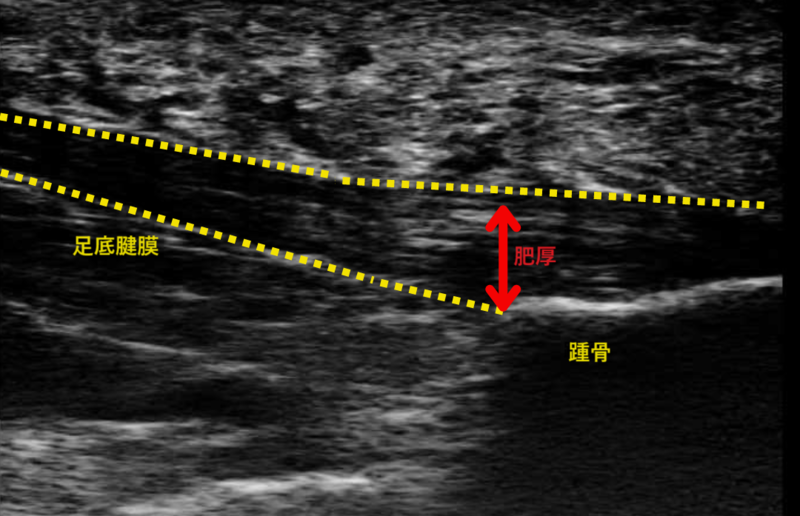

当院では、診察時にレントゲンと超音波検査、MRI等を用いて痛みの原因組織を特定し、それらに合った適切な治療を提案しています。足底腱膜炎では超音波で足底腱膜の肥厚やMRIで足底腱膜・脂肪体・踵骨の信号変化などを確認し、診断しています。これら画像所見の異常は変性(微細損傷)が起こっていることを示しており、また異常な神経線維の増殖によって痛みに対して過敏になっていることも考えられます。それらに対する有効性が報告されています。①短期的な除痛効果

踵に骨棘(骨のでっぱり)を認めます。この骨棘自体が痛みの原因ではないと多く報告されていますが、足底腱膜の硬さを判断する指標のひとつです。

足底腱膜の肥厚を認めます。